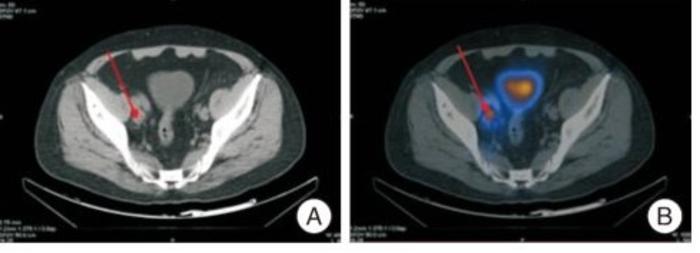

PSMA-PET/CT具有更高的灵敏度、特异度及转移灶的早期检出率,可对PCa进行精准分期,在PSA 水平较低时也能够有效发现转移病灶

对于接受前列腺根治术后生化复发的前列腺癌患者,

PSMA-PETPSA 水平0.2~0.5ng/ml,对于转移灶发现率为50%~57.9%

PSA水平 0.5~1.0ng/ml,对于转移灶发现率为58.3%~72.2%

PSA水平1.0ng/ml,对于转移灶发现率为75%